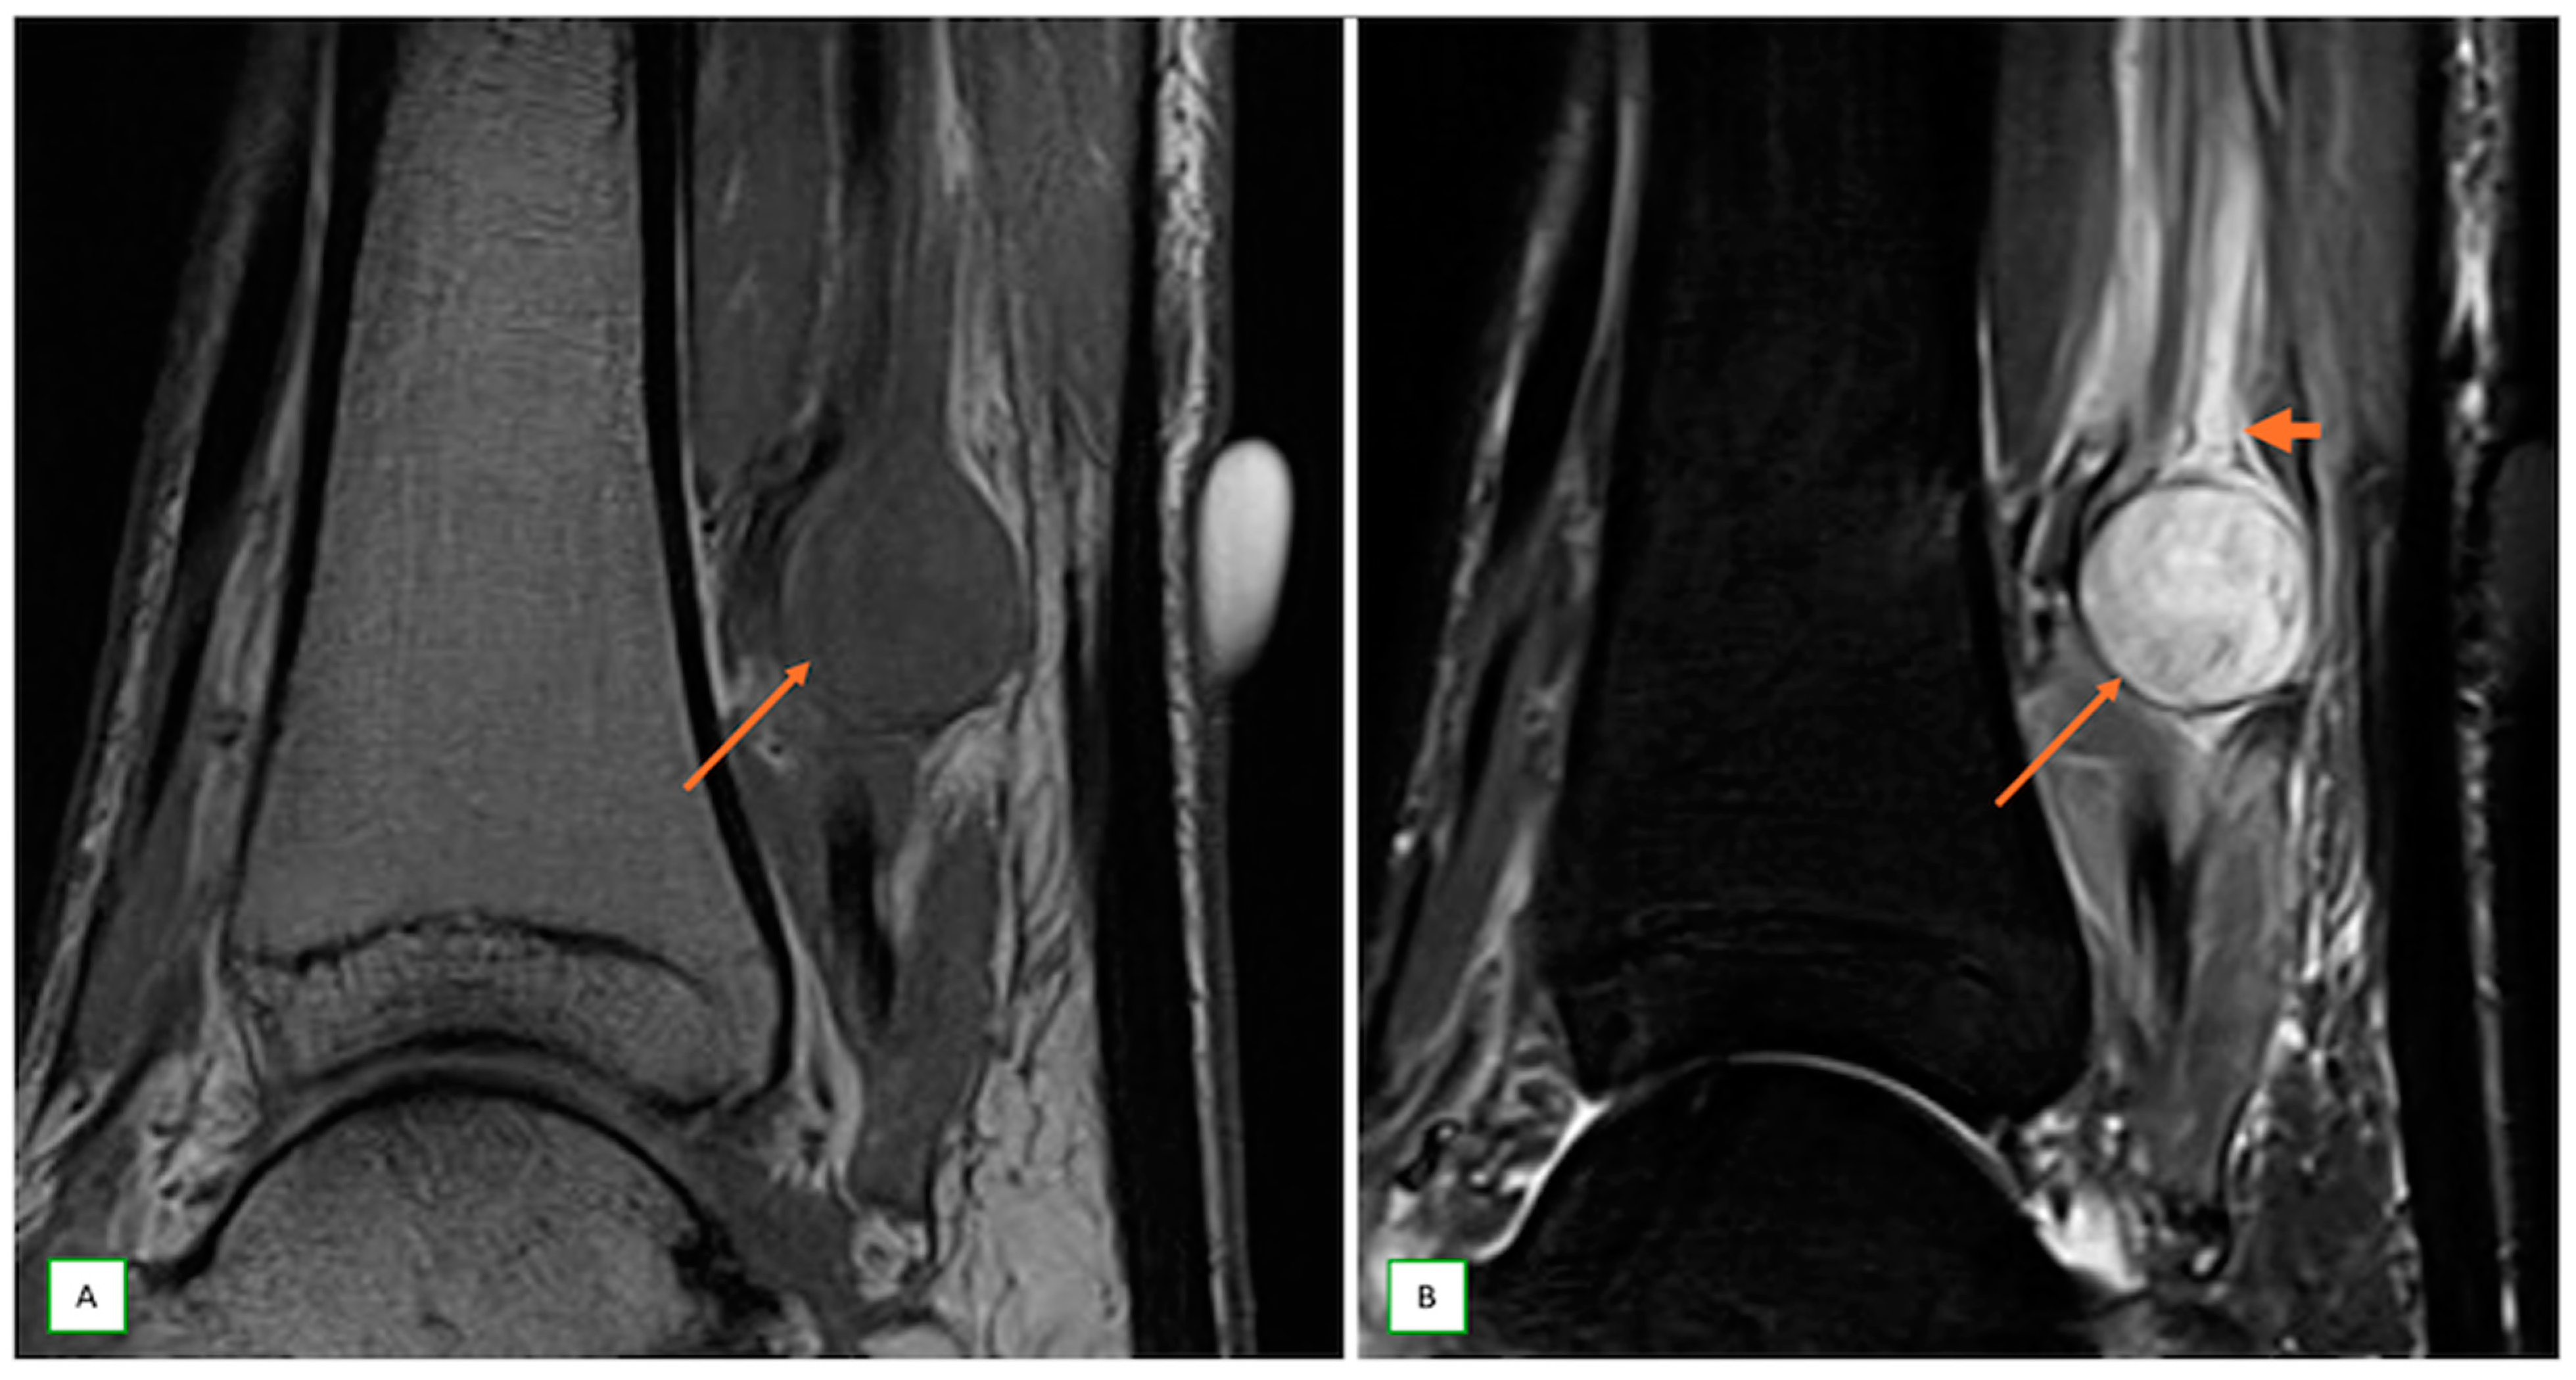

- Intraneural ganglion cysts usually occur near joints; are particularly common in the common peroneal nerve at the knee, owing to the intraarticular branch of the proximal tibiofibular joint; and appear as tubular, multiloculated cystic lesions following the course of the nerve on MRI [60,61] (Figure 16).